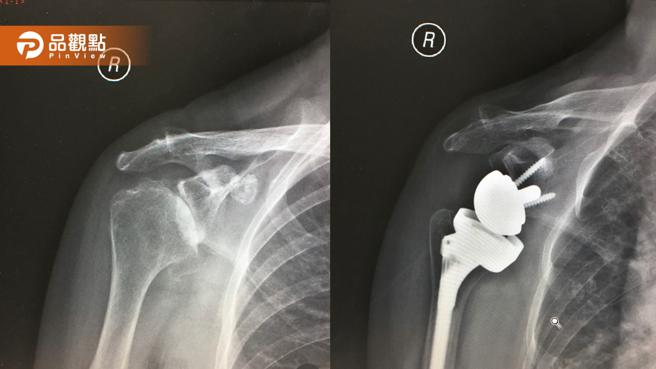

骨科医师廖志祥表示,反式人工肩关节是藉由与传统人工肩关节相反的特殊设计,把关节盂变成球头,肱骨变成凹窝,置换后可避开受损的旋转肌腱,而改由三角肌来恢復肩关节功能,让患者举高手臂。(图片来源:中正骨科)

反式人工肩关节在国外已行之多年,近10年才引进台湾,是藉由与传统人工肩关节相反的特殊设计,把关节盂变成球头,肱骨端变成凹窝,置换后可避开受损的旋转肌腱,而改由三角肌来恢復肩关节功能,让患者举起手臂。